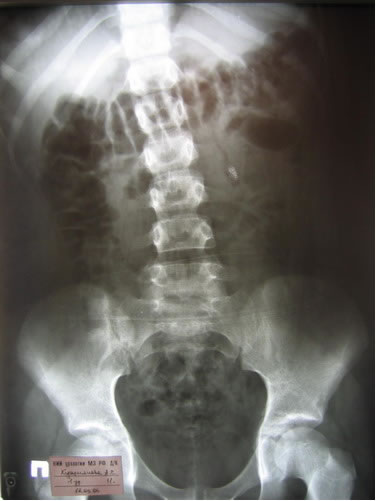

Обзорная, экскреторная урография